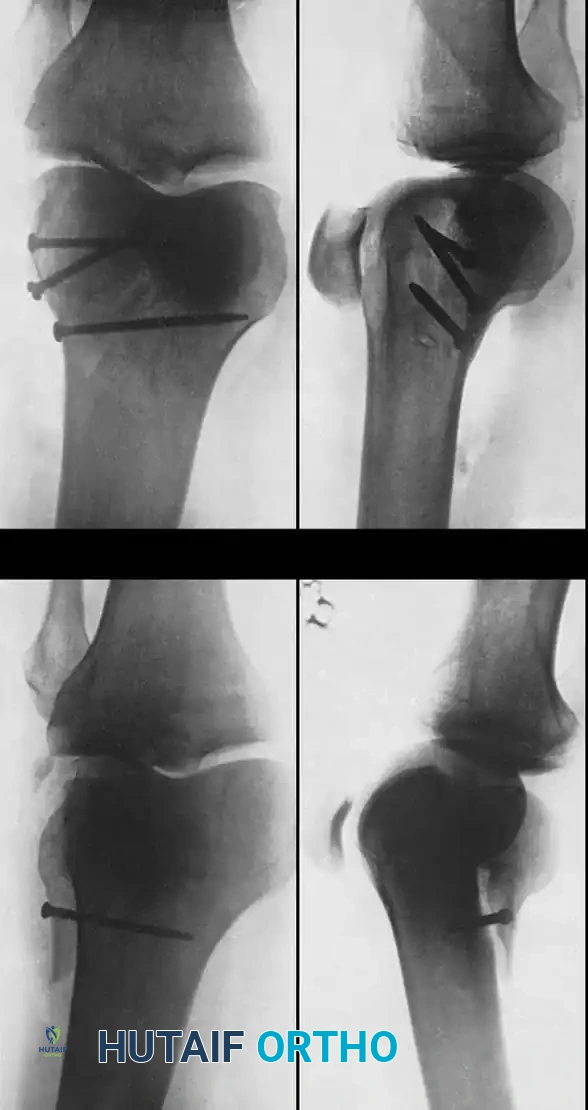

Fig. 51-76 A, Anatomy and surgical exposure. B and C, Intraoperative posteroanterior and lateral radiographs demonstrating successful screw fixation of the posterolateral condyle. (From Taitsman LA, Frank JB, Mills WJ, et al: Osteochondral fracture of the distal lateral femoral condyle: a report of two cases, J Orthop Trauma 20:358, 2006.)

Taitsman et al. reported successful outcomes for osteochondral fractures of the posterolateral femoral condyles treated with open reduction and internal fixation (ORIF) using countersunk screws. Preoperative Computed Tomography (CT) is mandatory to determine the exact size, location, and site of origin of the fragment.

6. Fixation: The fragment is anatomically reduced and provisionally stabilized with Kirschner wires. Definitive fixation is achieved using two 2.0-mm or 2.4-mm screws.

7. Countersinking: It is critical that the screw heads are countersunk 2 to 3 mm below the articular cartilage surface to prevent iatrogenic kissing lesions on the opposing articular surface.